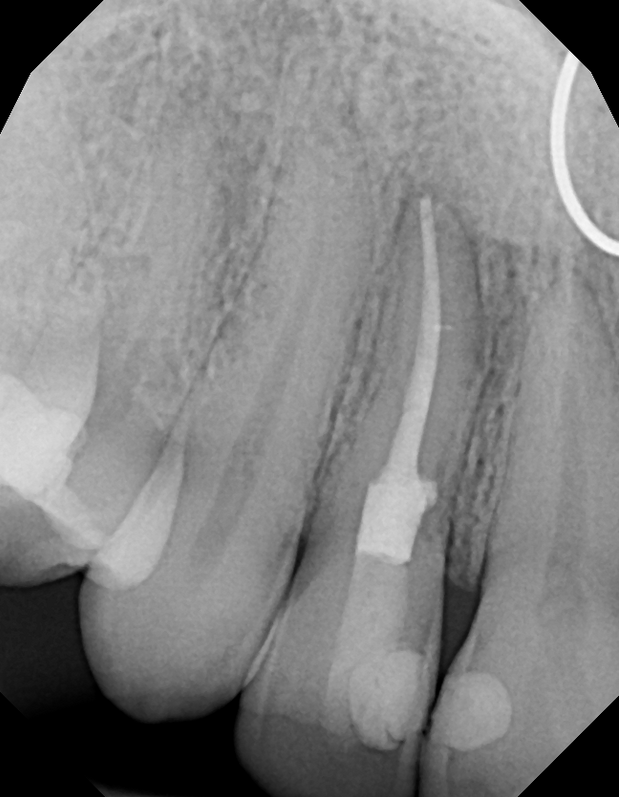

#7 NS-RCT (with SI retrieval)